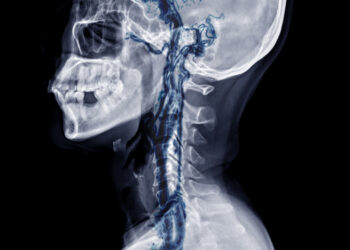

Skaityti daugiauDetailsVertebrobazilinis nepakankamumas – tai būklė, kai smegenų užpakalinėje dalyje esančios kraujagyslės nepatenka arba sumažėja kraujo pritekėjimas. Dėl to sutrinka pusiausvyros...

Skaityti daugiauDetailsStuburo arterijos disekcija – tai reta, tačiau pavojinga būklė, kuri pasireiškia, kai viena ar daugiau stuburo arterijos sienelių sluoksnių įplyšta....